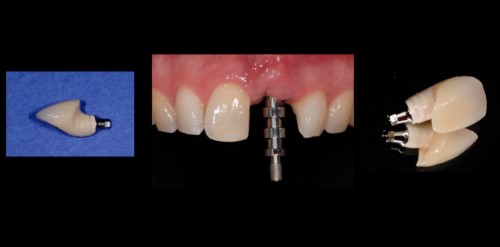

For the prosthetic restoration of single toaoth implants, a variety of treatment options exists: Metal or ceramic abutments, screw-retained or cemented crowns, all-ceramic or metal-ceramic crowns etc. This module will guide you through these treatment options and help you to take evidence-based decisions.

• Discuss the restorative treatment options for implant single crowns in esthetic and non-esthetic areas and their benefits and limitations

• Perform conditioning procedures of the peri-implant soft tissues in esthetic and non-esthetic areas

• Evaluate the esthetic impact of different abutment and crown materials

•  Decide which type is best suitable in esthetic and non-esthetic areas